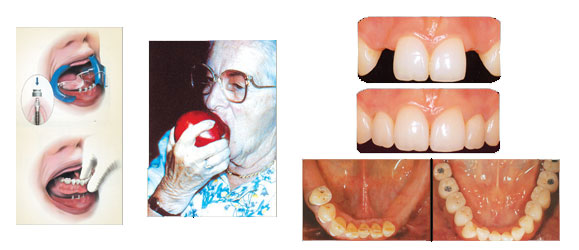

ایمپلنت دندان فوری و با ضمانت مادام العمر

- استفاده از روش Over denture

- حداقل ایمپلنت دندان

- حداقل زمان

- احساس واقعی دندان طبیعی

امروزه ایمپلنت دندان برای این به کار می رود که همانند یک دندان طبیعی زیبا و کاراست و دوامی برابر با دندان طبیعی دارد. شایان ذکر است که در بسیاری از بیماران، بی دندان به علت اثراتی که بر عملکرد دهانی و شرایط روحی و روانی بیمار می گذارد نوعی معلولیت محسوب می شود. مطالعات دراز مدت نشان داده میزان موفقیت عملکرد ایمپلنت دندان در فک پایین 95% و در فک بالا 93% است.

با استفاده از روش overdenture بیماران محترم با حداقل زمان احساس واقعی دندان طبیعی را احساس خواهد کرد. روش جدید immediate implantation (کاشت سریع) که ایمپلنت دندان درست پس از کشیدن دندان جای گذاری شود. در صورتی که ضخامت استخوان و سلامتی استخوان ایده آل باشد در حداقل زمان بیماران صاحب دندان های طبیعی و زیبا و کار آمد خواهد شد. امروز با بهره گیری از جدیدترین وسایل تشخیص از جمله توموگرافی کامپیوتری و سه بعدی و ساخت مدل راهنما کیفیت- کمیت استخوان و تعیین موفقیت درمان ایمپلنت دندان وتعیین زاویه قرارگیری ایمپلنت دندان به راحتی برای تیم کاشت دندان میسر است.